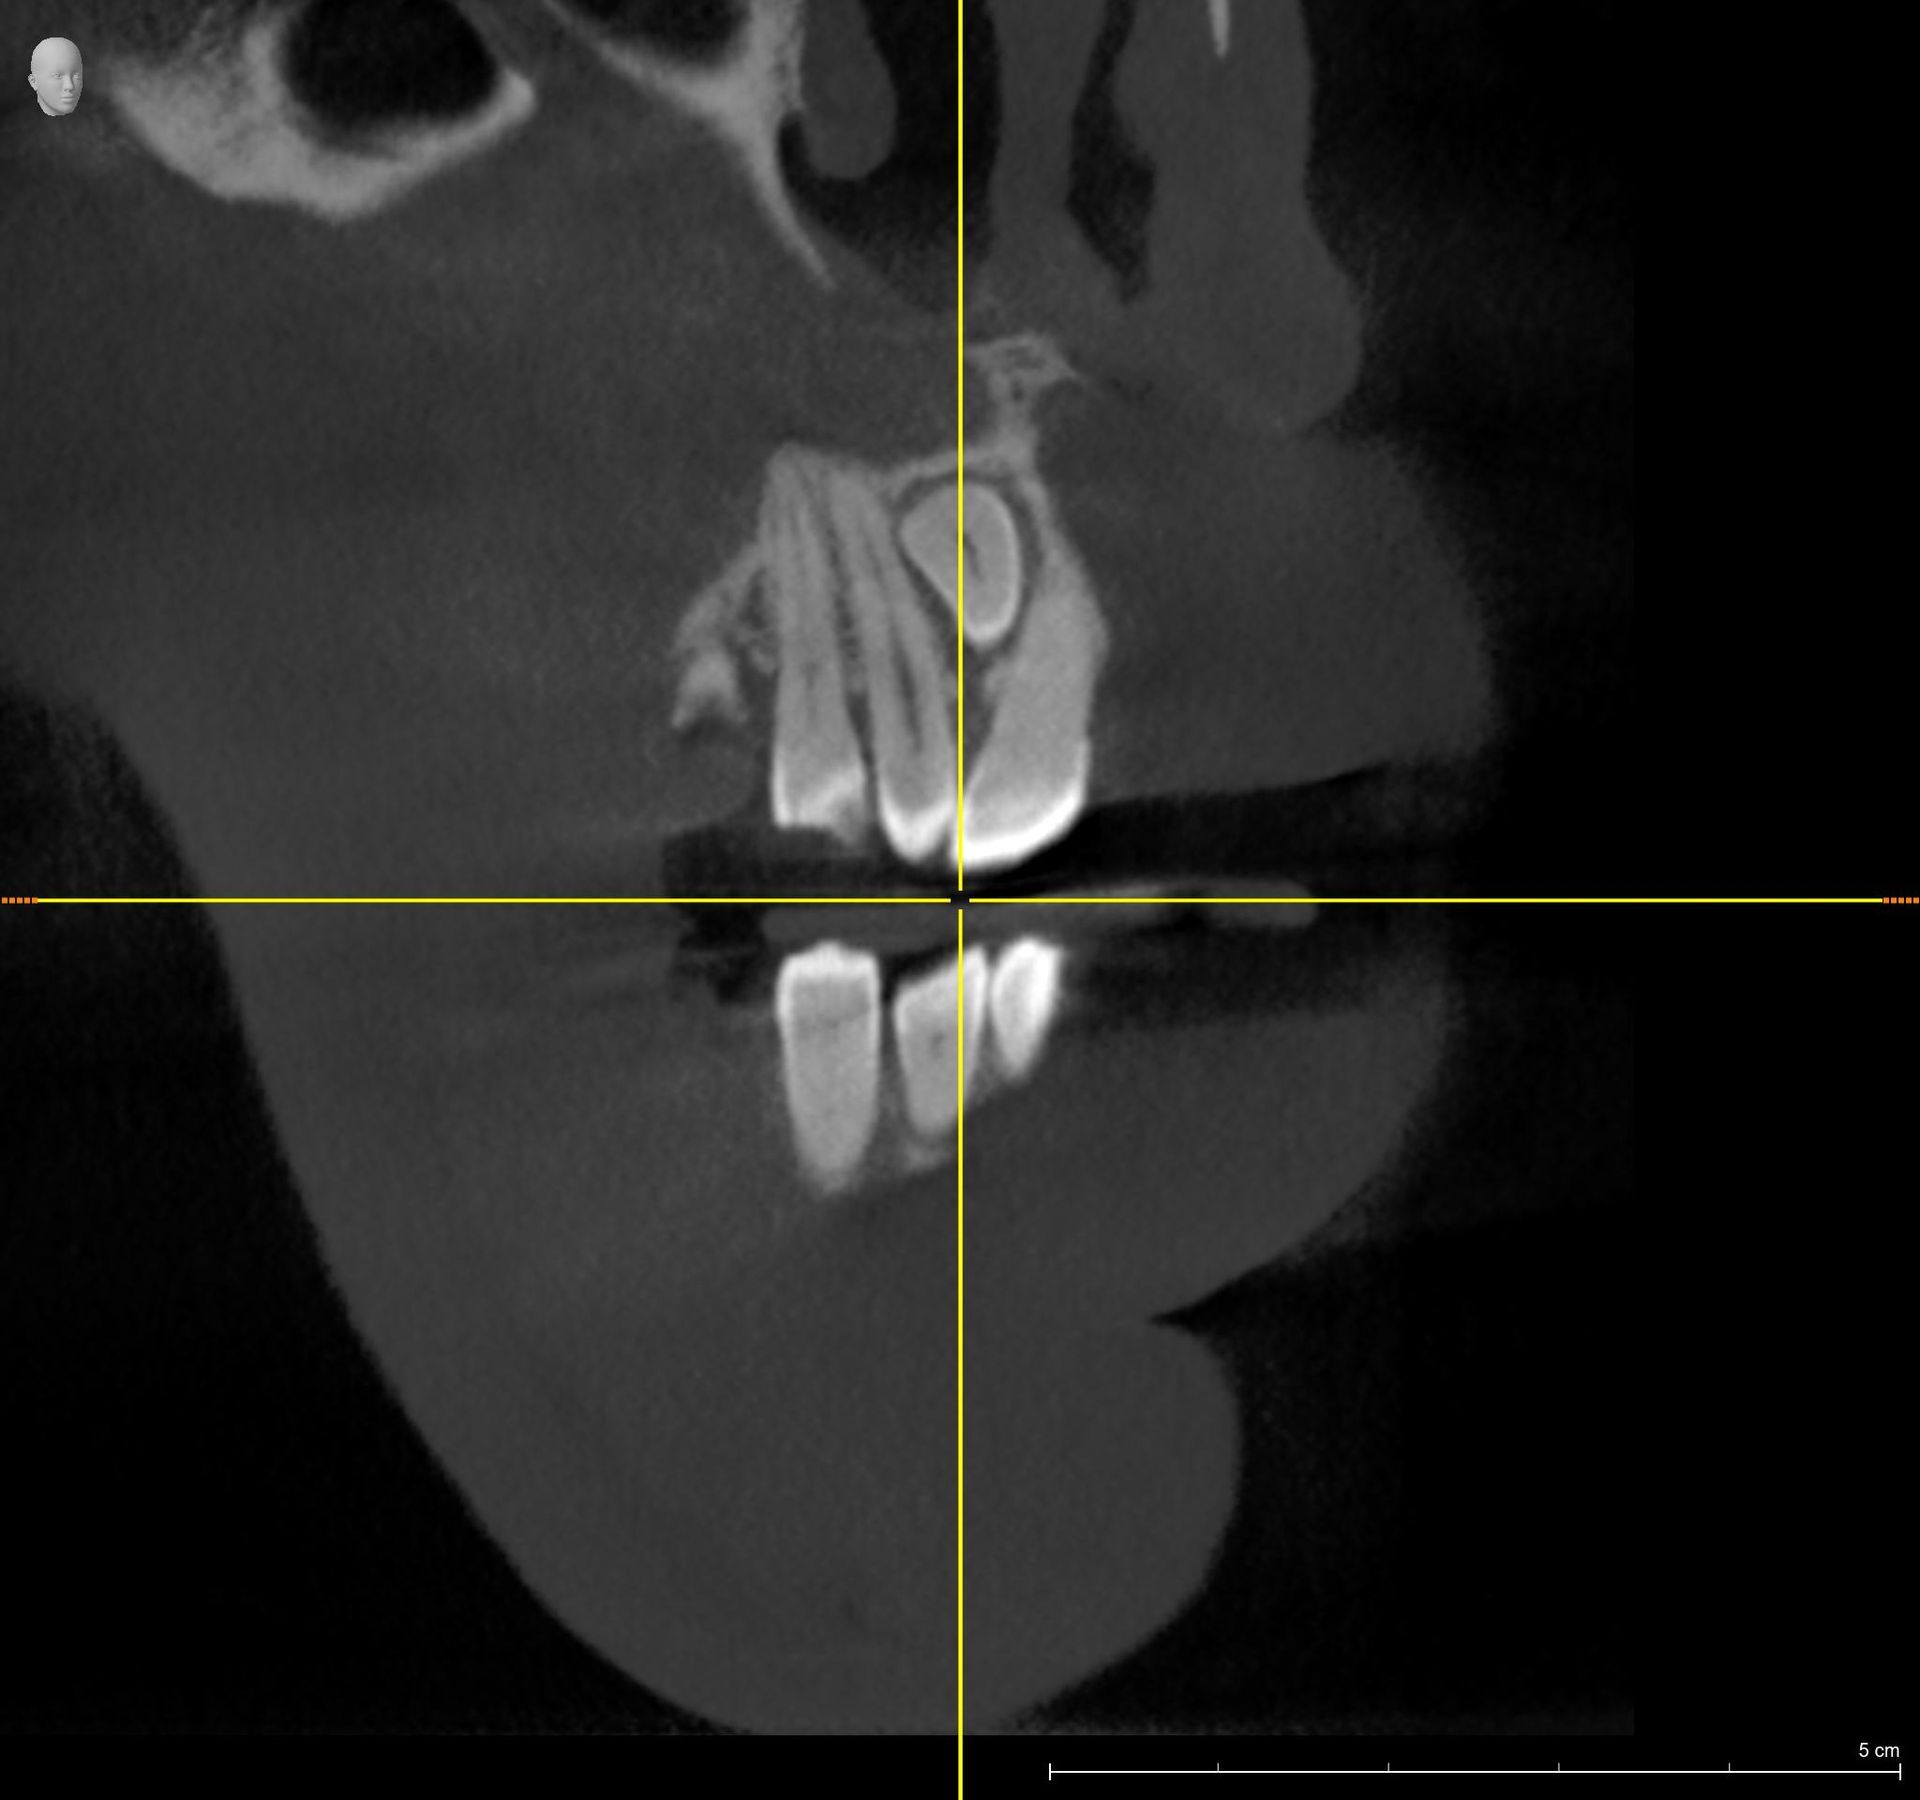

Esame diagnostico che permette di valutare, con precisione, la densità ossea mascellare e mandibolare, richiesto dai dentisti, in quanto indispensabile prima di un intervento di implantologia.

Trova indicazione anche in ortodonzia per lo studio dei denti inclusi, soprannumerari ed ectopici e in endodonzia.

La funzione 3D, permette la visualizzazione completa delle strutture dentarie, ossee, in tre dimensioni, con ottima risoluzione di contrasto per lo studio dei tessuti molli.